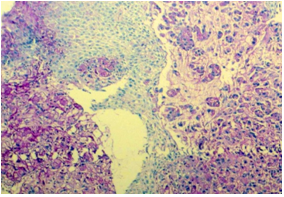

Figure 10 Mucin secreting adenocarcinoma (PAS, 100X).

In our study, out of 45 cases positive for malignancy on biopsy in upper GIT, 36(80%) cases were squamous cell carcinoma(SCC), 7(16%) cases were adenocarcinoma, 1 was of neuroendocrine tumour (2%) and 1 case was of poorly differentiated carcinoma(2%). Out of 39 cases positive for malignancy on cytology, 20(51%) cases were squamous cell carcinoma, 3(8%) were adenocarcinoma, 1(3%) was of small cell carcinoma, 4(10%) cases were poorly differentiated carcinoma and 11(28%) were unspecified carcinoma. Studies by Kaur et al.11 and Vidyavathi et al.5 also showed squamous cell carcinoma being the most common malignancy in upper GIT.